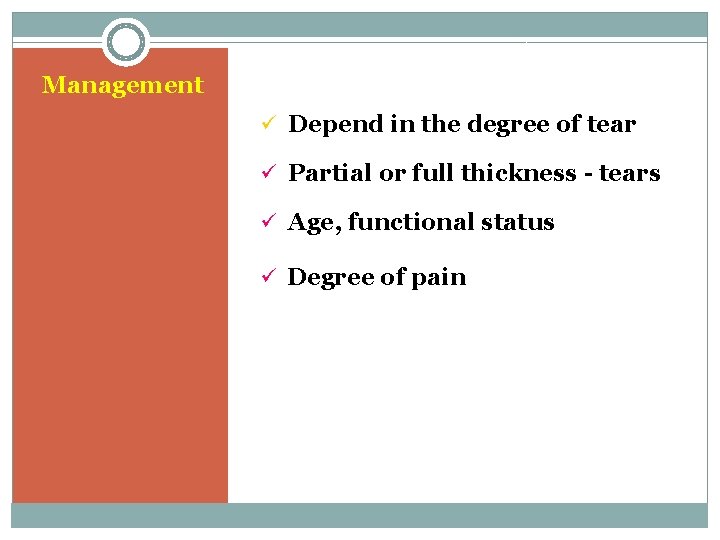

Management ü Depend in the degree of tear ü Partial or full thickness - tears ü Age, functional status ü Degree of pain